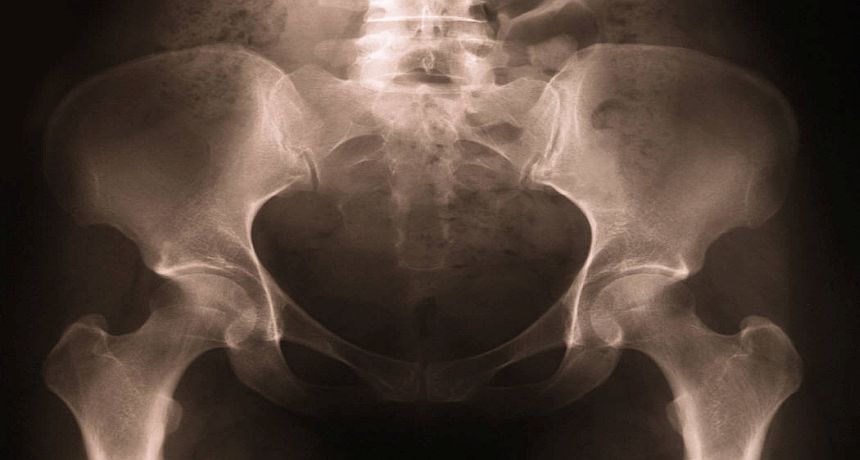

Russian Doctors can repair damaged bones using 3D printers and Bio-cement, which would later transform into the recipient’s own tissue.

In an official press release by the ‘Russian National Research Nuclear University’, it was stated that scientists have developed a

new technique to convert animal bones into material that can substitute for the damaged parts of human bones.